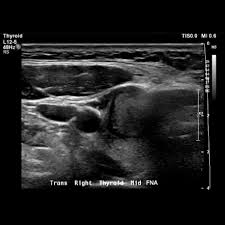

Air and bone also reflect sound waves. A lump in the neck —cancers that begin in the head or neck usually spread to lymph nodes in the neck before they spread elsewhere. A neck ultrasound may help diagnose (find): Breast ultrasound images are seen from superficial (skin) to deep (chest wall muscle) over a segment of tissue. A neck ultrasound can be used to observe the thyroid gland to look for nodules, growths, or tumors. But now i am worried that the reason the lump didn't show on the ultrasound is because it is actually under the skin in my neck (i.e in my throat) rather than on my actual thyroid/neck. David dang answered 14 years experience radiology node, cyst or others: A small lump on the neck usually is a lymph node, a small sebaceous cyst or a lipoma, although it could be something else. The most common symptom of thyroid cancer is a hard lump on the neck—but most patients experience no symptoms at all. This means that they are larger than about 1 centimeter (about 1/2 inch) across. Optimal positioning and exposure of the neck for ultrasound of the thyroid and parathyroid glands (a, b) and lateral neck for lymph node examination and mapping (c).while the vast majority of patients are supine on the exam table with a pillow supporting the shoulders to allow gentle neck extension, keep in mind that some patients have beautiful anatomy (d) that allows ultrasound exam even in. 1), and the presence of an echogenic hilus within lymph nodes was previously considered a sign of benignity. What does a healthy kidney look like on an ultrasound?

If your cancer diagnosis is based on an ultrasound, it could easily be wrong. But ultrasound is usually the first choice for looking at the thyroid and neck structures. Other causes for a neck mass may be due to cancers such as lymphoma, thyroid or salivary gland cancer, skin cancer, or cancer that has spread from somewhere else in the body. Cancerous lymph nodes can occur anywhere on the neck and are typically described as firm, painless, and sometimes may be immovable. As thyroid cancer gets more advanced, you might notice symptoms like: Cancerous neck masses in adults are most often due to head and neck squamous cell carcinoma (hnscc). An ultrasound of the neck is used to examine the carotid arteries located on each side of a patient's neck. Optimal positioning and exposure of the neck for ultrasound of the thyroid and parathyroid glands (a, b) and lateral neck for lymph node examination and mapping (c).while the vast majority of patients are supine on the exam table with a pillow supporting the shoulders to allow gentle neck extension, keep in mind that some patients have beautiful anatomy (d) that allows ultrasound exam even in. On ultrasound, a breast cancer tumor is often seen as hypoechoic, has irregular borders, and may appear spiculated. And my neck look like an old shapai. The breast tissue kind of looks like waves on the ocean. But now i am worried that the reason the lump didn't show on the ultrasound is because it is actually under the skin in my neck (i.e in my throat) rather than on my actual thyroid/neck. In the framework of such terms as ultrasound of the neck, can be performed the following studies:

Ultrasound an ultrasound is sometimes used, especially to look at the thyroid, salivary glands and lymph glands in the neck. The camera remains attached either to a flexible tube called endoscope or to a probe, while it passes within an opening in your body, often your mouth. Fna is generally done on all thyroid nodules that are big enough to be felt. The most common symptom of thyroid cancer is a hard lump on the neck—but most patients experience no symptoms at all. A 'neck check' is a simple procedure that can be done just about anywhere. Doctors and pathologists do not use internal ultrasound scan frequently to detect lymphoma. But i feel great and feel comfortable in my own skin. A small lump on the neck usually is a lymph node, a small sebaceous cyst or a lipoma, although it could be something else. What does a healthy kidney look like on an ultrasound? Thyroid nodules, or lumps, are very common.most aren't cancer. My doctor told me i could hide the scars away, but i don't wanna. And my neck look like an old shapai. Other ultrasound findings that suggest breast cancer include: